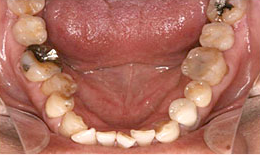

治療前

下顎

インプラントを2本埋め込んで、セラミックスクラウンを被せた